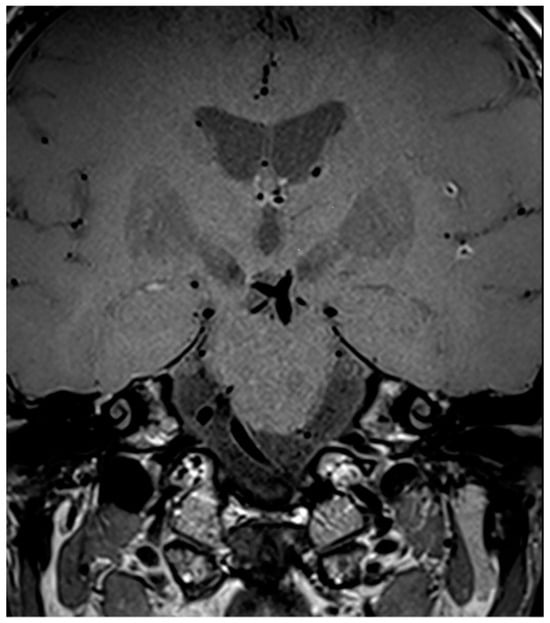

3.2. Primary Central Nervous System Vasculitis

3.3. MRI Findings

3.4. Secondary Central Nervous System Vasculitis